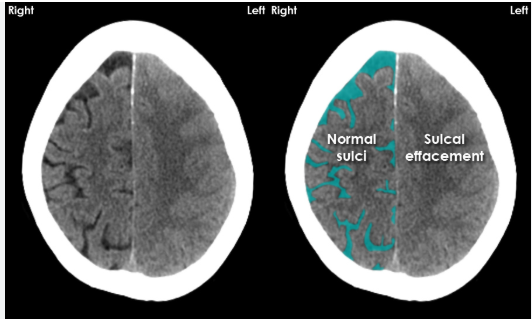

15

In CT head interpretation, what does ‘Be’ refer to and what are the main findings?

1. Sulcal effacement

What does sulcal effacement look like on a CT head, and what conditions does it indicate?

Sulcal effacement: Loss of normal, symmetrical gyral-sulcal pattern of brain tissue

Indicates increased intracranial pressure